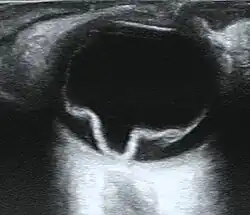

Ultrasound showing a retinal detachment

If the view of the retina is not clear, imaging techniques such as ultrawide-field fundus photography, B-scan ultrasonography, and optical coherence tomography (OCT) may help to identify a detachment.[8][13][14] Fundus photography provides a detailed view of the back of the eye, potentially revealing retinal tears or breaks.[8][16] On B-scan ultrasonography, a detached retina typically appears as a membrane floating in the vitreous cavity, moving in a wave-like motion.[19] OCT can detect fluid behind the retina, involvement of the macula (the central part of the retina), and other abnormalities within the retinal layers.[8][20]